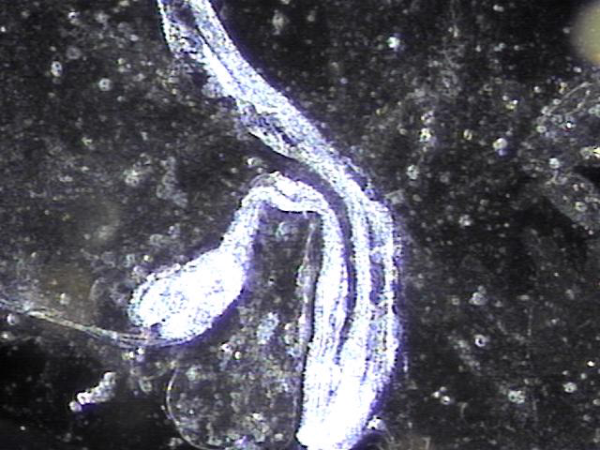

주 2회 전립선의 표적 치료후 사정관 입구에 막혀 있던 탈락된 상피세포와 사정관 벽에 쌓여 있던 상피 세포 덩어리가 치료 된후 관찰한 현미경학적 자료입니다.

This is a microscopic image taken after twice-weekly targeted prostate treatments. It shows the successful removal of shed epithelial cells that had been blocking the opening of the ejaculatory duct, as well as a buildup of epithelial cell clusters that had accumulated along the duct walls.